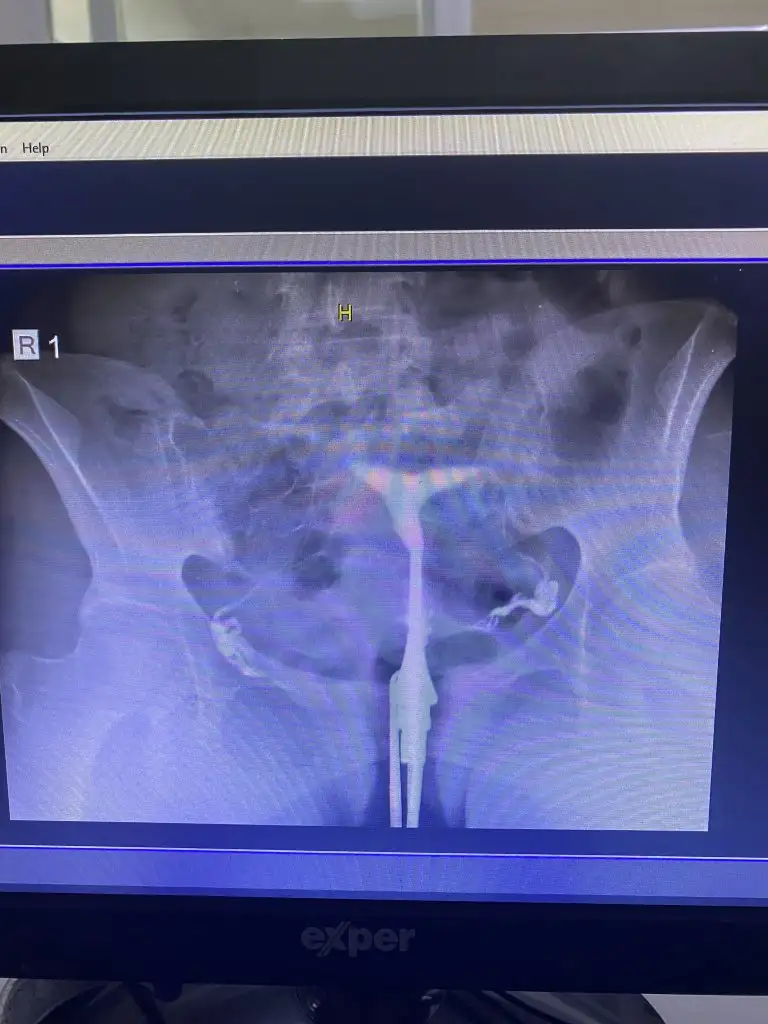

Arkadaşlar 4 tane düşüğüm var.pıhtılaşma sorunum var ama sonkinde oksopar,pruloton,progestan,coraspirin kullandığım halde kalbi durdu.hepsinin kalbi 7-8 haftalarda durdu.en son gittiğim doktor rahim şeklimin bozul olduğunu söledi.kafamı karıştırdı.ameliyat olmam gerekiyomu?düşükler bundanmı?benim gibi olan varmı?

• 389B690A-7178-4B84-AB0E-5C1730360482.webp

• E1D082F7-C057-4B7B-BC2E-3B1EC52EE89E.webp

• 70F5CE45-FF1D-48F9-9C0A-2A7F5750028A.webp